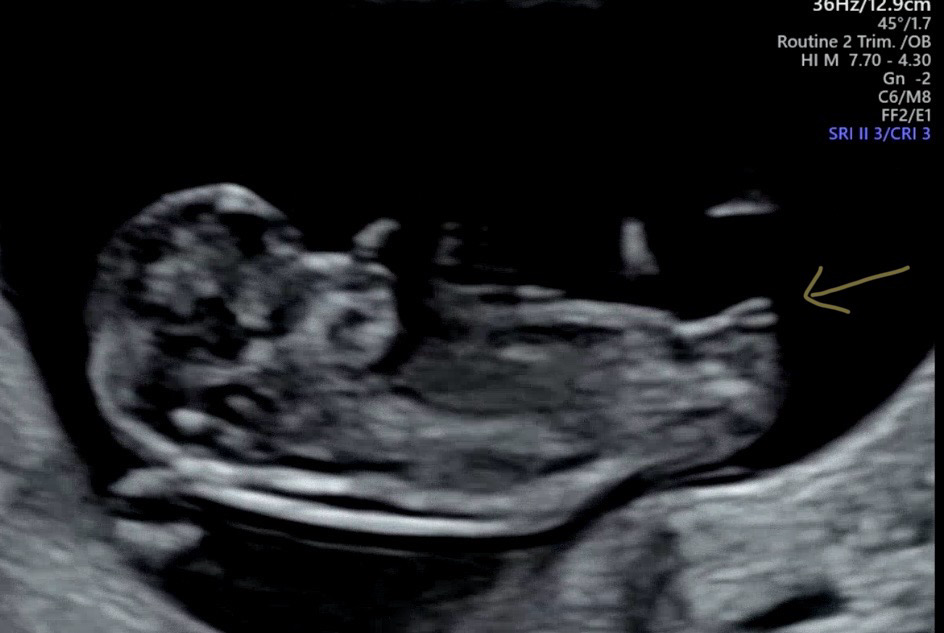

생식결절이 두갈래로 진행되고 있었어요! 딸일지 아들일지 넘 기대되요🥰 민간요법으로 딸 낳으려고 노력많이했는데 일부러 니프티는 안했어요 ㅠㅠ 이제 2차 기형아때 알 수 있을텐데 넘 궁금해요..💕

게시글 사진은 12주 기형아검사하면서 찍은거에요! 댓글 감사합니당 ✿˘◡˘✿